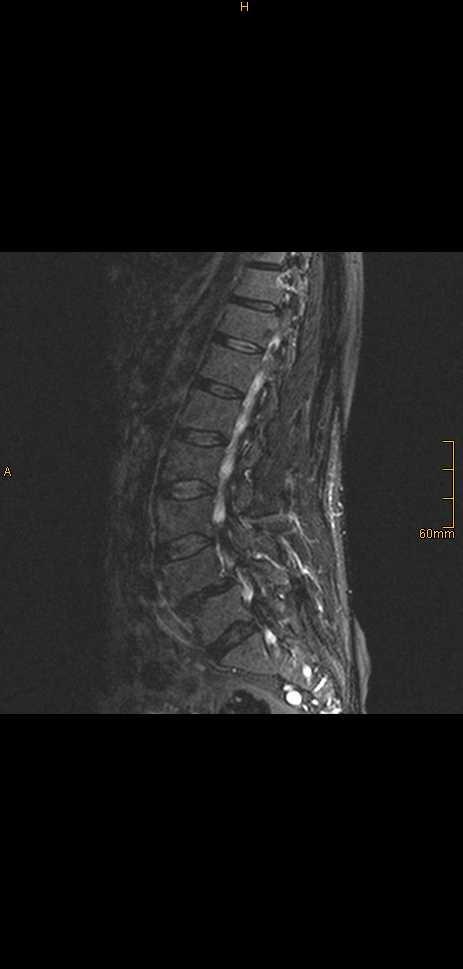

Magnetic resonance imaging demonstrated two intracerebral lesions. The symptomatic lesion was removed microneurosurgically and histology demonstrated a metastasis from a malignant peripheral nerve sheath tumor. Postoperatively, whole-brain irradiation was performed. The primary tumor was identified in the area of the sciatic nerve on the right. Follow-up 14 months after resection showed that there was no progression of the intracerebral lesions but an increase in size and number of distant metastases.

磁共振成像显示两个脑内病变。有症状的病变通过显微神经外科手术切除,组织学检查显示为恶性外周神经鞘瘤转移。术后进行了全脑照射。原发肿瘤在右侧坐骨神经区域被发现。切除术后14个月的随访显示,脑内病变无进展,但远处转移灶的大小和数量增加。